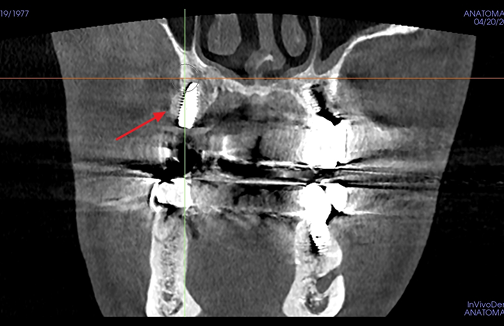

연세준치과는 숙련된 의료진의 경험과 첨단 디지털 장비로

데이터 기반의 과학적인 분석과 예측을 통해

더욱 빠르고 정확한 결과를 제공합니다.

어려운 케이스일수록

자신 있습니다.

당뇨 · 고혈압 등 전신질환 수술을 받으신 분부터 재수술이 필요하신 분들까지.

원칙대로 진행한다면, 문제가 생길 수 없습니다.